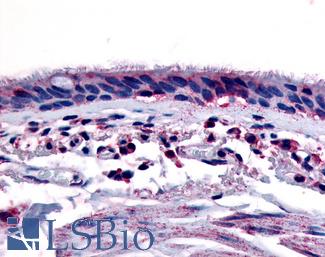

AHR

Anti-Aryl Hydrocarbon Receptor antibody LS-A3018 IHC of human respiratory epithelium and bronchial smooth muscle. Immunohistochemistry of formalin-fixed, paraffin-embedded tissue after heat-induced antigen retrieval.